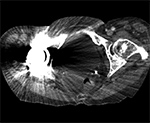

Figure 3A Figure 3B Figure 4A Figure 4B

Artifact summation Artifact summation Windowing Windowing

Artifact Summation. (A) Scout image demonstrates bilateral total hip arthroplasties. (B) Axial CT image at the level of acetabular cup and femoral head shows severe transverse streaking related to total summed attenuation of metal components. Optimal Windowing. (A) Axial CT image of the pelvis viewed in soft tissue windows demonstrates extensive streak artifact due to total hip arthroplasty prohibiting evaluation of adjacent bone and soft tissue structure. (B) Same axial CT image set to bone windows results in improved visibility of adjacent bone and soft tissue anatomy.